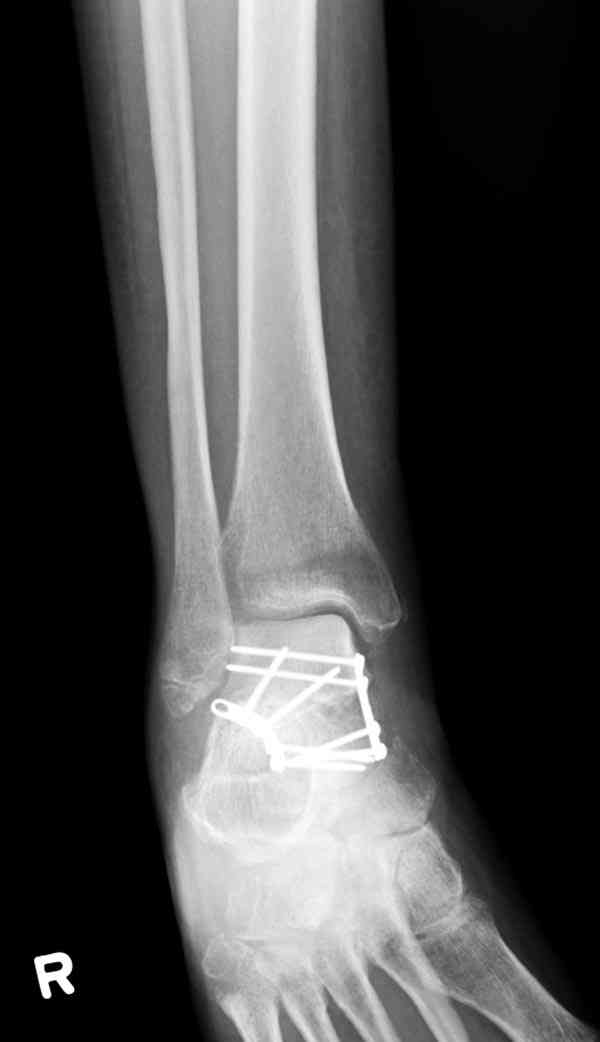

И второй случай из недавней ташкентской практики, (извините за качество ренгенограммы и только в одной проекции) случай падения с высоты (кстати моего друга - известного киноактера) - открытый

смещенный перелом тарана, с переломом переднего края дистального эпиметафиза большеберцовой кости.

При поступлении в приемной сделана первичная обработка с ушиванием открытой латеральной раны и вытяжением за пятку.

Из-за отсутствия времени пришлось оперировать на второе утро, из материала, что имеем на месте, фиксирован двумя шурупами, а третий-это контур сломанного жойстика в 4 мм. На дистальный медиальный конец тибиа antiglide 3.5 мм пластина. Через пару дней выписан и несмотря на предупреждение, самостоятельно начал нагрузку в 4 недели, время не ждет, снимается в боевике в Росийской Федерации.

Djoldas Kuldjanov, MD